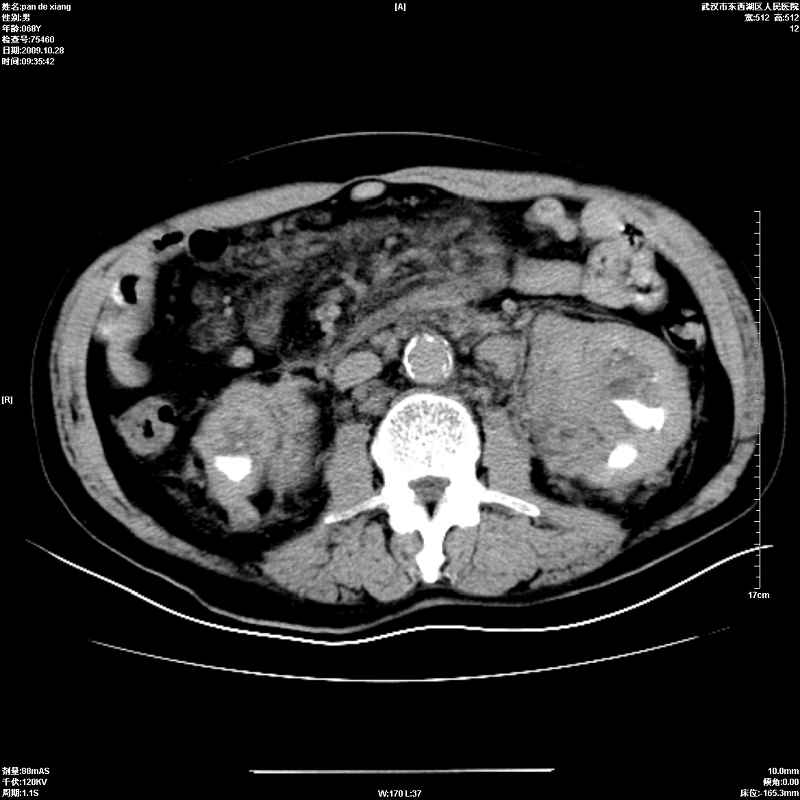

以下是引用杀毒软件在2009-10-28 20:41:00的发言:[br]结合临床考虑---白血病双肾改变或淋巴瘤。

以下是引用zxl51642在2009-10-29 9:59:00的发言:[br]结合临床“单克隆免疫球蛋白血症”,考虑双肾为继发损害并肾功能不全(尿中大量igg及少量iga、igm等大分子免疫球蛋白滤出所致继发损害),椎前软组织肿块为髓外造血。与浆细胞瘤有区别,平扫时有战友说的很清楚。